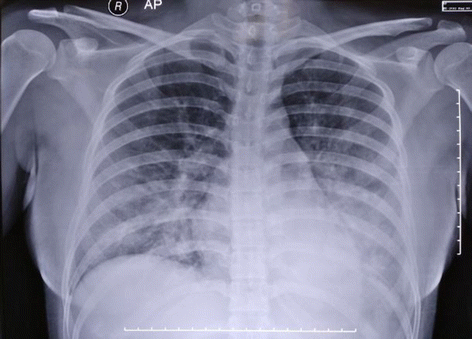

Case presentation: A 24-year-old primigravid Sundanese woman presented to our intensive care unit due to acute pulmonary edema secondary to massive plasma leakage caused by severe dengue. She tested positive for both immunoglobulin G and immunoglobulin M dengue serology indicating she had secondary dengue infection, which placed her at risk for an exaggerated cytokine response as was evident clinically. She had to undergo an emergency cesarean section which was later complicated by rebleeding and hemodynamic instability due to an atypical defervescence period. She was successfully managed by multiple blood transfusions and was discharged from our intensive care unit on day 8 without any negative sequel.